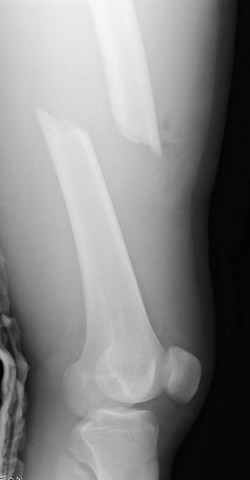

больному 42, автоавария, политравма, открытая черепномозговая травма, безсознании, открытый перелом бедра, размозжение мягких тканей, дефект кожи на передней поверхности бедра около 13 см2 от ожога, компартмент синдром.

По поводу открытого перелома больной ургентно взят на ретроградное интрамедулярное штифтование, после рутинного дебрайдмента и фасциотомии на бедре и на голени.

перелом бедра

интраоперационные

постоперационные

спасибо за урок, критику принимаю, постараюсь исправится. Уточнения: даты написаны автоматически и надо читать 14-19-24-28 Марта 2005 года, также хирургическая обработка вместе дебрайдмент. (фотографии рентгенограмм скопированы с цифрового ренгенологического архива, извините за качество)